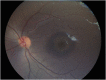

Results: A 6-year-old girl with thalassemia major who was on chronic multiple blood transfusions since 2 years of age presented with blurred vision in both eyes for 2 months. Blood reports showed very high serum ferritin levels in the range 400 to 2,250 ng/mL (checked every 3 months) since 4 years of age. She was on oral iron chelator deferasirox for 2 years, which was stopped a month ago. Fundus examination of both eyes showed a characteristic bull's eye macula with a purplish hue in the outer ring probably due to iron deposition. The center of the bull's eye had a beaten bronze appearance.